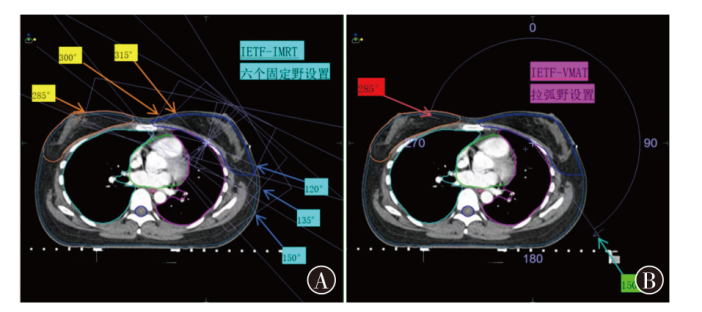

基于内缘切线野的调强放疗与容积弧形调强放疗在左侧乳腺癌保乳术后放疗中的剂量学研究

Dosimetric study of intensity-modulated radiotherapy and volumetric intensity modulated arc therapy based on the inner edge tangent field for radiotherapy after breast-conserving surgery of left-sided breast cancer

目的 探究左侧乳腺癌保乳术后基于内缘切线野(IETF)的调强放疗(IMRT)与容积弧形调强放疗(VMAT)的剂量学差异。方法 选取2022年6月至2023年6月收治于云南省肿瘤医院放射治疗科的35例左侧乳腺癌保乳术后行IMRT患者的定位CT和靶区危及器官(OAR)等资料,针对同一患者分别设计基于IETF的IMRT和VMAT两种放疗计划,IETF-IMRT和IETF-VMAT;对两种放疗计划的靶区和OAR剂量及计划执行时间进行比较。结果 靶区剂量:IETF-IMRT和IETF-VMAT两种放疗计划靶区的D98%分别为(47.92±0.51)、(48.21±0.33)Gy,D50%分别为(52.04±0.22)、(51.91±0.26)Gy,D2%分别为(53.93±0.36)、(53.62±0.41)Gy,适形指数分别为0.84±0.03、0.87±0.02,均匀性指数分别为0.12±0.01、0.10±0.01,差异均有统计学意义(t=-3.87,P<0.001;t=3.53,P=0.001;t=5.30,P<0.001;t=-13.60,P<0.001;t=6.24,P<0.001)。OAR剂量:IETF-IMRT和IETF-VMAT两种放疗计划左肺V5分别为(31.91±6.28)%、(33.99±6.31)%,V20分别为(11.71±2.06)%、(9.73±2.12)%,差异均有统计学意义(t=-4.18,P<0.001;t=12.40,P<0.001);右肺V5分别为(0.11±0.08)%、(7.13±3.12)%,Dmean分别为(1.05±0.12)、(2.71±0.27)Gy,差异均有统计学意义(t=-33.62,P<0.001;t=-13.30,P<0.001);脊髓D2%分别为(1.08±0.11)、(4.83±1.40)Gy,差异有统计学意义(t=-15.99,P<0.001)。左肺Dmean分别为(7.45±1.08)、(7.37±1.03)Gy,心脏Dmean分别为(4.21±0.96)、(4.41±0.48)Gy,右侧乳腺Dmean分别为(3.74±1.52)、(3.48±1.11)Gy,差异均无统计学意义(t=1.16,P=0.253;t=-1.76,P=0.088;t=1.41,P=0.169)。计划执行时间:IETF-IMRT和IETF-VMAT两种放疗计划执行时间分别为(10.73±1.21)、(2.18±0.17)min,差异有统计学意义(t=44.71,P<0.001)。结论 IETF-IMRT和IETF-VMAT均能满足临床要求,但两种技术各有特点。靶区适形性和均匀性方面,IETF-VMAT略优;两种计划的OAR剂量均显著低于乳腺癌术后放疗剂量限值,其中,IETF-IMRT计划的左肺V5,右肺V5、Dmean和脊髓D2%略低,IETF-VMAT计划的左肺V20略低。IETF-VMAT较IETF-IMRT显著缩短了计划执行时间,可极大地降低患者体位变化引起的剂量偏差,明显提高患者放疗体验感和舒适度;综合考虑,左侧乳腺癌保乳术后放疗IETF-VMAT较IETF-IMRT更具优势。

Objective To explore the dosimetry difference between intensity-modulated radiotherapy (IMRT) and volumetric intensity modulated arc therapy (VMAT) based on the inner edge tangent field (IETF) after left-sided breast conserving surgery. Methods The localization CT and target organ at risk (OAR) data of 35 patients with left-sided breast cancer treated with IMRT after breast conserving surgery at Department of Radiotherapy in Yunnan Cancer Hospital from June 2022 to June 2023 were selected. The IETF-IMRT and the IETF-VMAT plans were designed for the same patient based on IETF, the dosimetry differences of target areas and OAR, as well as the planned execution time were compared between the two groups. Results Dosimetry of target areas: for IETF-IMRT and IETF-VMAT, the D98% of the planning target volume were (47.92±0.51) and (48.21±0.33) Gy, respectively, while the D50% were (52.04±0.22) and (51.91±0.26) Gy, respectively, and the D2% were (53.93±0.36) and (53.62±0.41) Gy, respectively, the conformity index were 0.84±0.03 and 0.87±0.02, respectively, while the homogeneity index were 0.12±0.01 and 0.10±0.01, respectively, with statistically significant differences (t=-3.87, P<0.001; t=3.53, P=0.001; t=5.30, P<0.001; t=-13.60, P<0.001; t=6.24, P<0.001). Dosimetry of OAR: for IETF-IMRT and IETF-VMAT, the left lung V5 were (31.91±6.28)% and (33.99±6.31)%, respectively, and the V20 were (11.71±2.06)% and (9.73±2.12)%, respectively, with statistically significant differences (t=-4.18, P<0.001; t=12.40, P<0.001). The right lung V5 were (0.11±0.08)% and (7.13±3.12)%, respectively, and the Dmean were (1.05±0.12) and (2.71±0.27) Gy, respectively, with statistically significant differences (t=-33.62, P<0.001; t=-13.30, P<0.001). The spinal cord D2% were (1.08±0.11) and (4.83±1.40) Gy, respectively, with a statistically significant difference (t=-15.99, P<0.001). The left lung Dmean were (7.45±1.08) and (7.37±1.03) Gy, the heart Dmean were (4.21±0.96) and (4.41±0.48) Gy, and the right-sided breast Dmean were (3.74±1.52) and (3.48±1.11) Gy, respectively, with no statistically significant difference (t=1.16, P=0.253; t=-1.76, P=0.088; t=1.41, P=0.169). Planned execution time: the execution time of IETF-IMRT and IETF-VMAT was (10.73±1.21) and (2.18±0.17) min, respectively, with a statistically significant difference (t=44.71, P<0.001). Conclusion Both IETF-IMRT and IETF-VMAT can meet clinical requirements, however the two techniques have their own characteristics. IETF-VMAT has better conformity and homogeneity of target region. The planned OAR dosimetry in both plans are significantly lower than the dose limit of postoperative radiotherapy for breast cancer, among which the left lung V5, the right lung V5, Dmean and spinal cord D2% of IETF-IMRT are slightly lower, the left lung V20 of IETF-VMAT is slightly lower. IETF-VMAT significantly reduces the planned execution time compared with IETF-IMRT, thus can greatly reduce the dose deviation caused by patient position change, and significantly improve patients experience and comfort of radiotherapy. Taken together, IETF-VMAT has advantages over IETF-IMRT in radiotherapy after breast conserving surgery of left-sided breast cancer.